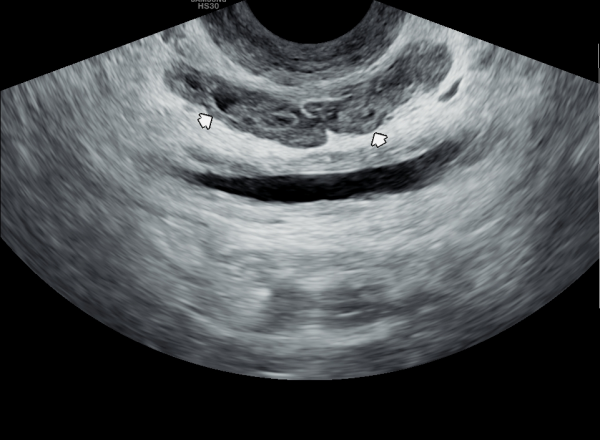

내원 첫날 정면 경직장 전립선 초음파 정낭의 검사상 사정관 입구의 순환 장애로 정낭의 낭종이 관찰되는 초음파 사진입니다.

This is a transrectal prostate ultrasound image taken on the first visit, showing a cyst in the seminal vesicle caused by a circulation blockage at the entrance of the ejaculatory duct.

4개월 가량 주 2회 정낭의 표적 치료후 정낭의 낭종들이 감소하고 순환되는 추적 경직장 전립선 초음파 사진입니다.

This is a follow-up transrectal prostate ultrasound image taken after approximately four months of twice-weekly targeted treatment of the seminal vesicles. The image shows that the cysts in the seminal vesicles have decreased and circulation has improved.